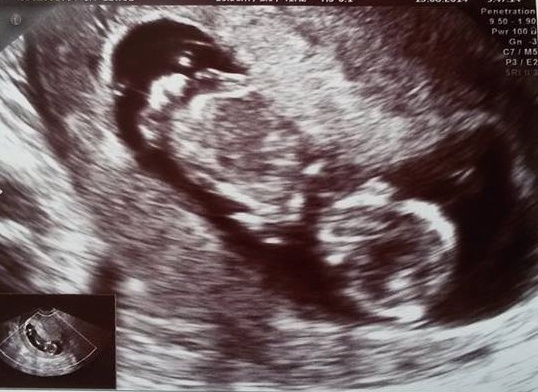

Dneska jsme byli na screeningu.Mimčo se nechtělo ukázat a v pohodě si spinkalo,ale nakonec jsme to nějak zvládli.Můj první syn byl uplně stejnej a to pohodářství mu zůstalo doteď. Přikládám fotečku a bude to kluk :) Takže jmeno bude oříšek,ale mi něco vymyslíme asi ale až na porodním sále